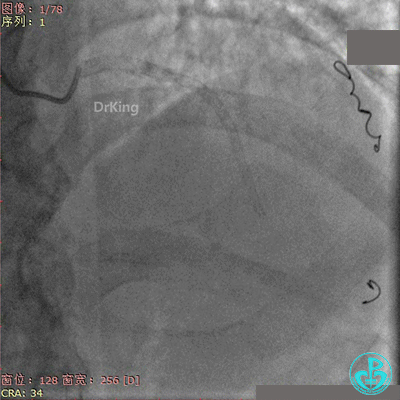

右冠脉支架通畅无狭窄,右冠脉给前降支远端提供逆向侧支循环。

EBU指引导管左冠脉造影显示粗大前降支中段闭塞,闭塞段近端有对角支发出,前降支同侧逆向显影,闭塞段不长。